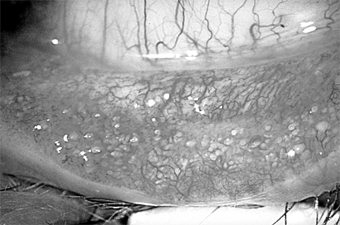

Figure 5-18

Figure 5-18: Multiple concretions on the inferior tarsus. These are often associated with chronic lid disease caused by staphylococcal species.